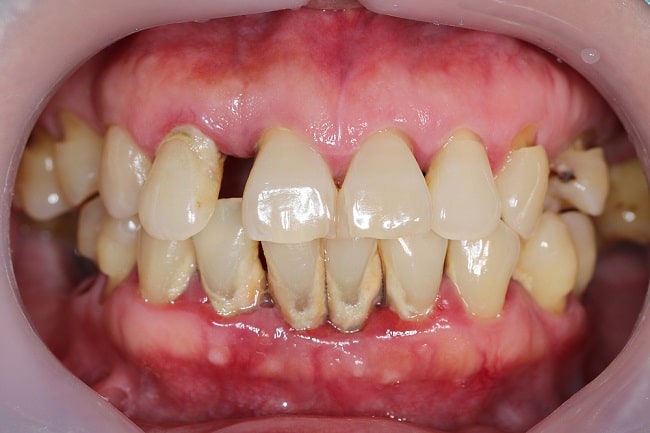

Gejala yang sering dialami oleh penderita adalah rasa tidak nyaman saat mengunyah, merasa mudah berdarah saat menyikat gigi atau mengunyah sesuatu, dan terkadang disertai rasa sakit. Tanda klinis periodontitis umumnya adalah peningkatan probing depth sulkus gingiva, perdarahan saat probing (bleeding on probing), hilangnya perlekatan gingiva (attachment loss), serta resorbsi tulang alveolar baik secara vertikal maupun horizontal.[4]

Diagnosis periodontitis dapat ditegakkan dengan melakukan pemeriksaan intraoral dan pemeriksaan penunjang rontgen panoramik atau orthopantomograph (OPG). Pemeriksaan intraoral yang mengarah kepada periodontitis adalah sulkus gingiva yang menunjukkan kedalaman lebih dari 4 mm, bleeding on probing positif, hingga kegoyahan gigi. Dari pemeriksaan penunjang berupa rontgen panoramik, akan terlihat adanya resorbsi tulang alveolar.[5]